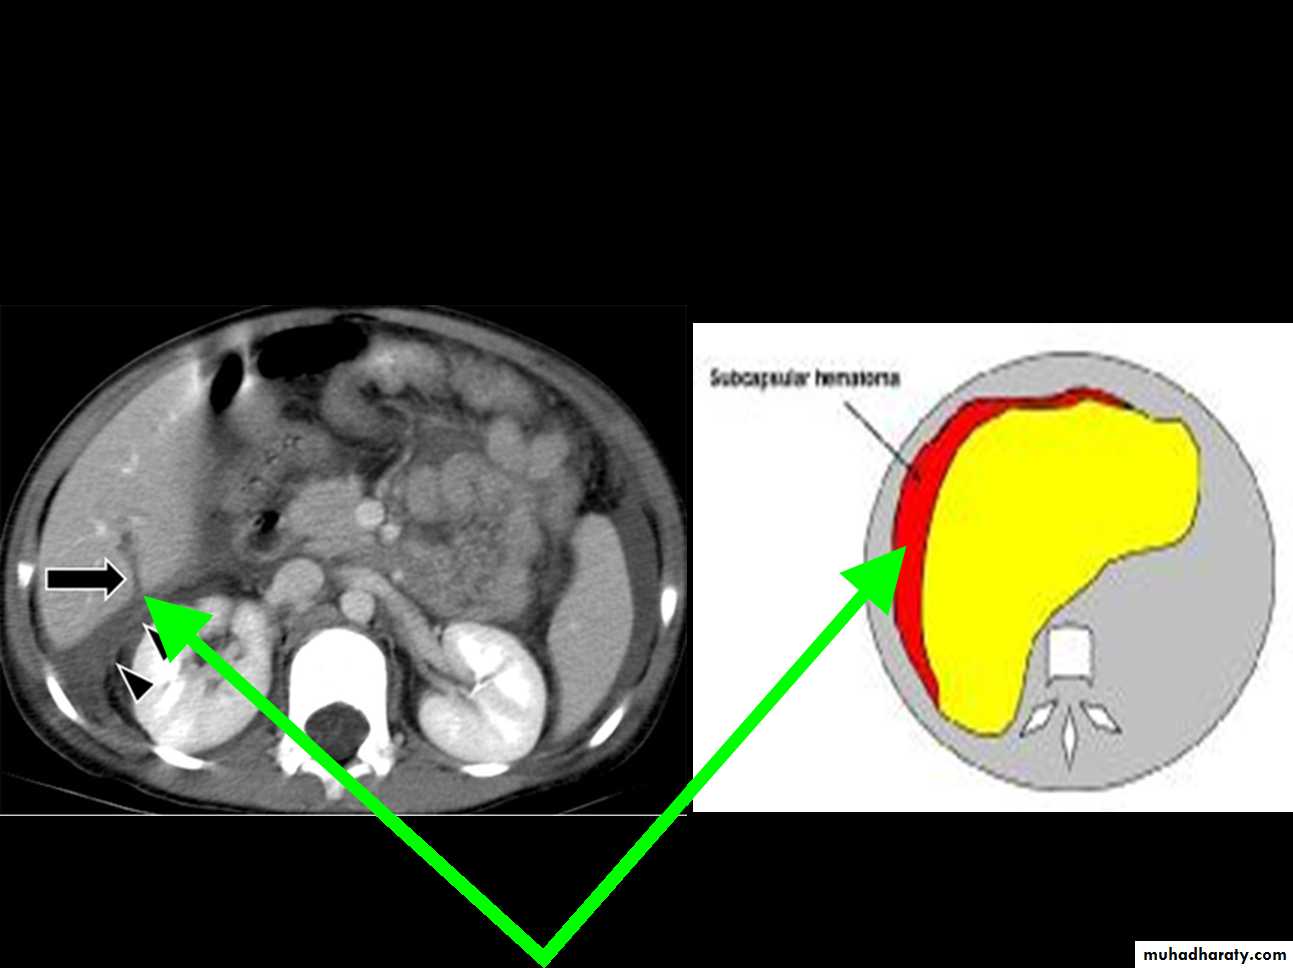

CT Scans

Accurate in localizing the site of liver injury and any associated injuries

Used to monitor healing

CT criteria for staging liver trauma uses AAST liver injury scaleGrades 1-6

Subcapsular hematoma

Laceration

Contusion